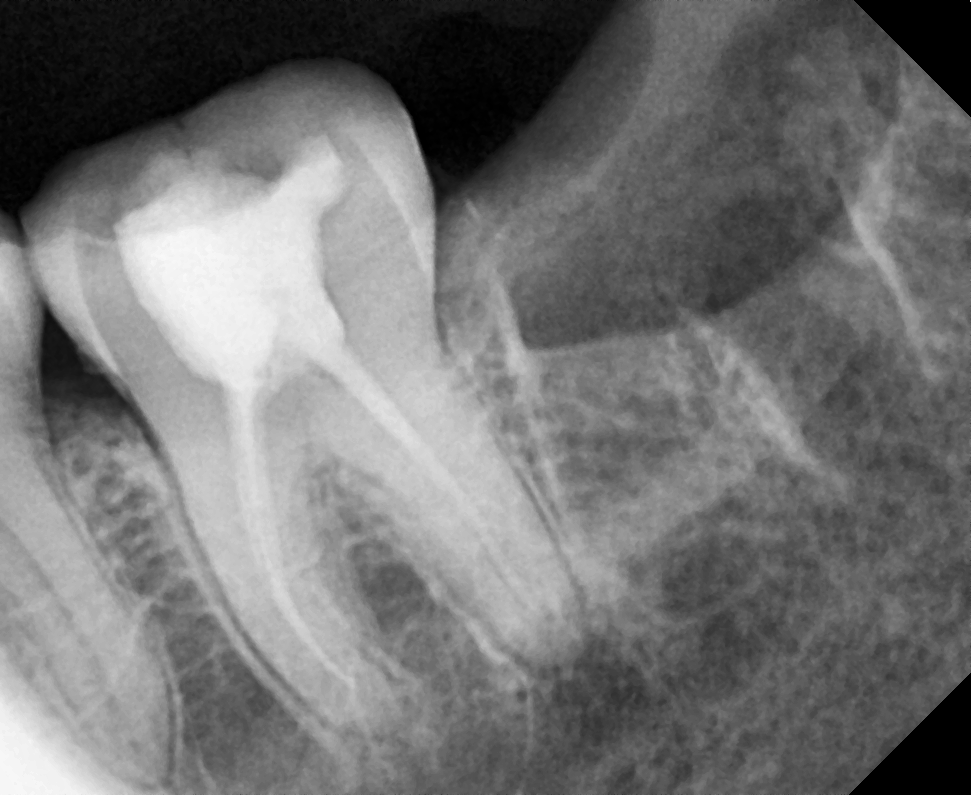

Lower 3rd Molar

After After

Before Before